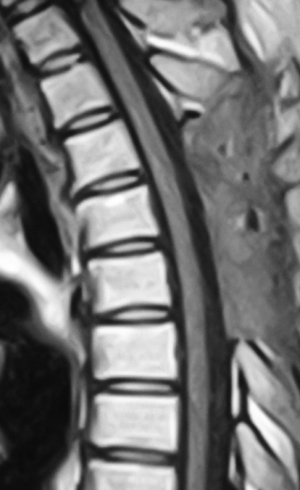

腰部脊柱管狭窄症の手術前 |

腰部脊柱管狭窄症の手術後 | ||